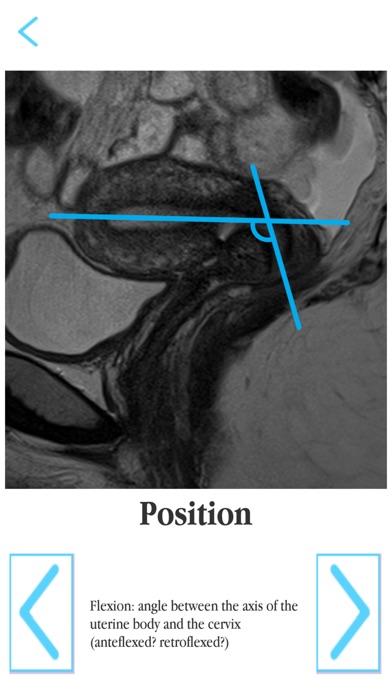

- learn mode: Annotated illustrations of the female pelvis correlated with MRI scans

- test mode: Test yourself using the interactive MRI examinations with highlighted anatomical structures